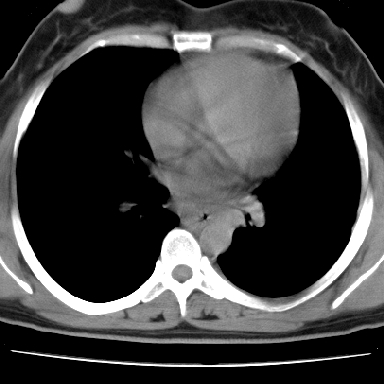

f 37 咳嗽1周,咯血1次,无浓痰,无明显发热

左下肺肿块影,内可以见小泡征,并见厚壁空洞形成,洞内缘可见壁结节。靠近胸膜侧可见胸膜肥厚粘连。双肺可见多发性小结节影。

考虑:左下空洞性肺癌伴两肺转移

偏心性厚壁空洞,壁结节,胸膜肥厚粘连,双肺多发性小结节灶。这么多典型征象,即使错了也错的有道理!

左下肺有空洞,壁厚薄不均,壁结节,两肺多发小结节影,腋窝下可疑淋巴结肿大,综上所述考虑周围性肺癌并两肺转移可能性大,建议穿刺活检。

支持癌性空洞:壁厚,无液平,内壁不规则,外壁呈分叶状,较大,偏心性,壁结节,胸膜凹陷,转移灶。